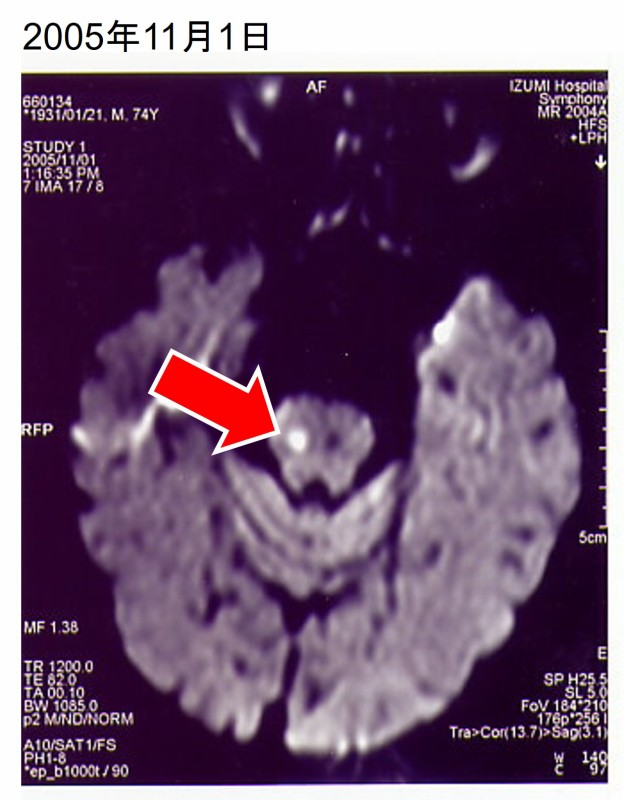

2005年11月1日、眼の焦点が合わず、下肢脱力感が出現したため、泉病院脳神経科へ緊急入院となった。

(3)MRI拡散強調画像にて右側中脳の新鮮梗塞 → 中脳の障害。

本症例でも、MRAで脳底動脈の描出不良がみられており、両側中脳の梗塞が生じているものと判断される。拡散強調画像における右側中脳の高信号と左眼内転障害は、その結果と思われる。この脳底動脈閉塞病変の原因としては、塞栓が多いと言われている。

(2)中脳の障害は、脳底動脈の分岐部の閉塞により、両側中脳への細小動脈の血流不全が生じて発生したものと推測される。拡散強調画像における右側中脳の高信号、並びに左眼内転障害はこれらの表れと解釈できる。